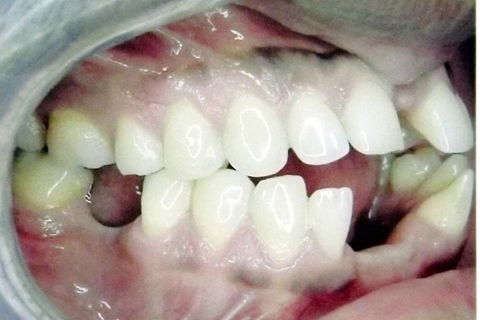

fotos finais, paciente encaminhado para implantes.

Paciente do sexo masculino, 36 anos, brauifacial. Relatava que os Diastemas lhe incomodavam muito, e em tratamento anterior o profissional fez exo de 2 incisivos centrais inferiores e instalou Prótese movel com 4 incisivos, após um tempo de uso a prótese começou a incomodar. em planejamento com o implantodontista ficou definido o fechamento dos diastemas e reabilitação dos elementos 41 e 31 com implantes.

segue as fotos do caso